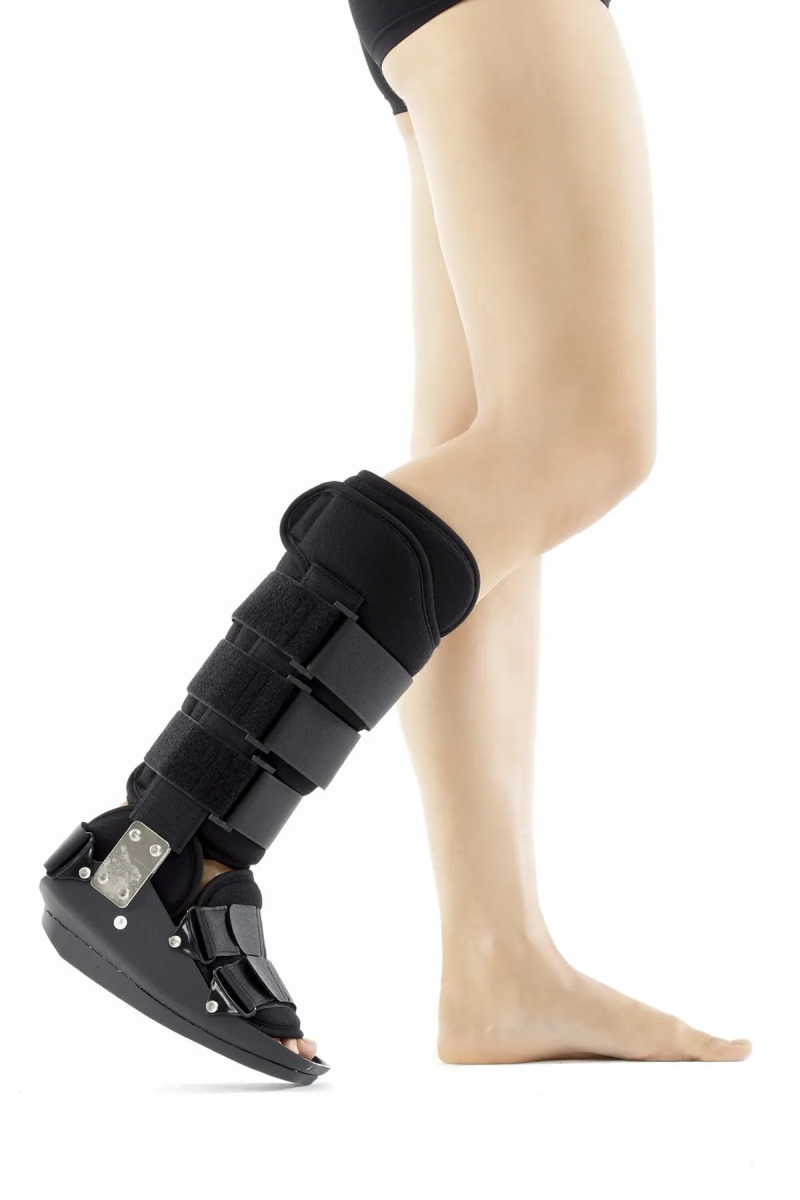

Destek veya Yürüme Alçısı: Yırtılmış bir Aşil tendonunun cerrahi olmayan tedavisi, yaralı ayağın ve ayak bileğinin hareketsiz hale getirilmesini gerektirir. Alçı ve bu durum için özel tasarlanmış botlar kullanarak ameliyatsız tedavi yapmak mümkündür.

Bu şekilde enfeksiyon yara sorunları ve ameliyata ait diğer olası risklerden korunmak mümkün olmasına rağmen yetersiz iyileşme sonucu tekrar kopma gibi dezavantajları da vardır.